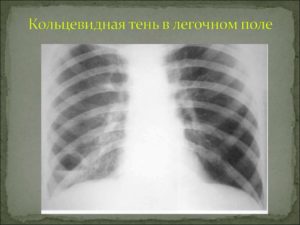

Синдром кольцевидной тени

Кольцевидное пятно на легком на рентгене, является наиболее простым для выполнения анализа синдромом. Как правило, кольцевидная тень появляется на рентгене в результате формирования полости, наполненной воздухом.

Обязательным условием, при котором обнаруженное затемнение относят к синдрому кольцевидной тени – это сохранение замкнутого кольца при выполнении снимков во всех проекциях и в различных положениях тела пациента.

Если хотя бы на одном из серии снимков кольцо не будет иметь замкнутое строение, тень можно считать оптической иллюзией.

При обнаружении полости в легком следует оценить равномерность и толщину ее стенок. Так, при большой и равномерной толщине контура, можно предполагать воспалительное происхождение полости, например, туберкулезная каверна.

Аналогичная картина наблюдается при абсцессе, когда происходит гнойное расплавление тканей с удаление содержимого через бронхи.

Однако при абсцессе, остатки гноя, чаще всего, продолжают находиться в полости и их полное удаление довольно редкое явление, поэтому обычно такая полость – это туберкулезная каверна.

Неравномерно широкие стенки кольца свидетельствуют о процессе распада рака легкого. Некротические процессы в опухолевой ткани, могут вызвать образование полости, но поскольку некроз развивается неравномерно, опухолевые массы остаются на внутренних стенках полости, создавая эффект «неравномерности» кольца.

Важно! Основной сложностью при оценке кольцевидной тени, является определение локализации образования, так как в большинстве случаев подобный синдром наблюдается при внелегочных процессах (деформация ребер, газы в кишечнике, газы в плевральной полости).